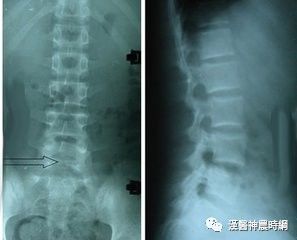

脊柱不仅仅是支撑你的身体、缓冲身体的压力和震荡以及保护内脏的器官;脊椎的病变也不仅仅是引起颈腰部的疼痛和麻木;它还可以引起心律失常、头痛眩晕、胃痛腹泻、血压增高、性功能障碍……目前发现,有超过百种的疾病与脊椎有关。

人的脊椎一旦异常,可以出现诸多看上去与脊椎毫不相关的内脏疾病。这些疾病涉及内科、外科、神经科、内分泌科、妇科、儿科、耳鼻喉科、眼科、口腔科及皮肤科等。许多病人辗转多家医院,多个科室,疾病未能得到根本的诊治,就是由于未能解决脊椎病变的原因。下面是我在临床中遇到的临床个案,虽然它们的症状千奇百怪,但都有一个共同点:都是脊椎惹的祸。

脊柱神经医学认为:脊柱是身体的大梁,脊神经是神经系统的中枢,是大脑和小脑的延伸。如果脊柱的椎体或者脊神经或血管有了卡压或障碍(主要来自于左右的偏歪以及上下的挤压),人的健康就会受到不同程序的影响,导致人体的不适或五脏六腑的病变。目前,已经发现有上百种疾病与脊柱力学平衡有关,这些疾病涉及到人体神经、呼吸、消化、泌尿、内分泌等各个系统。